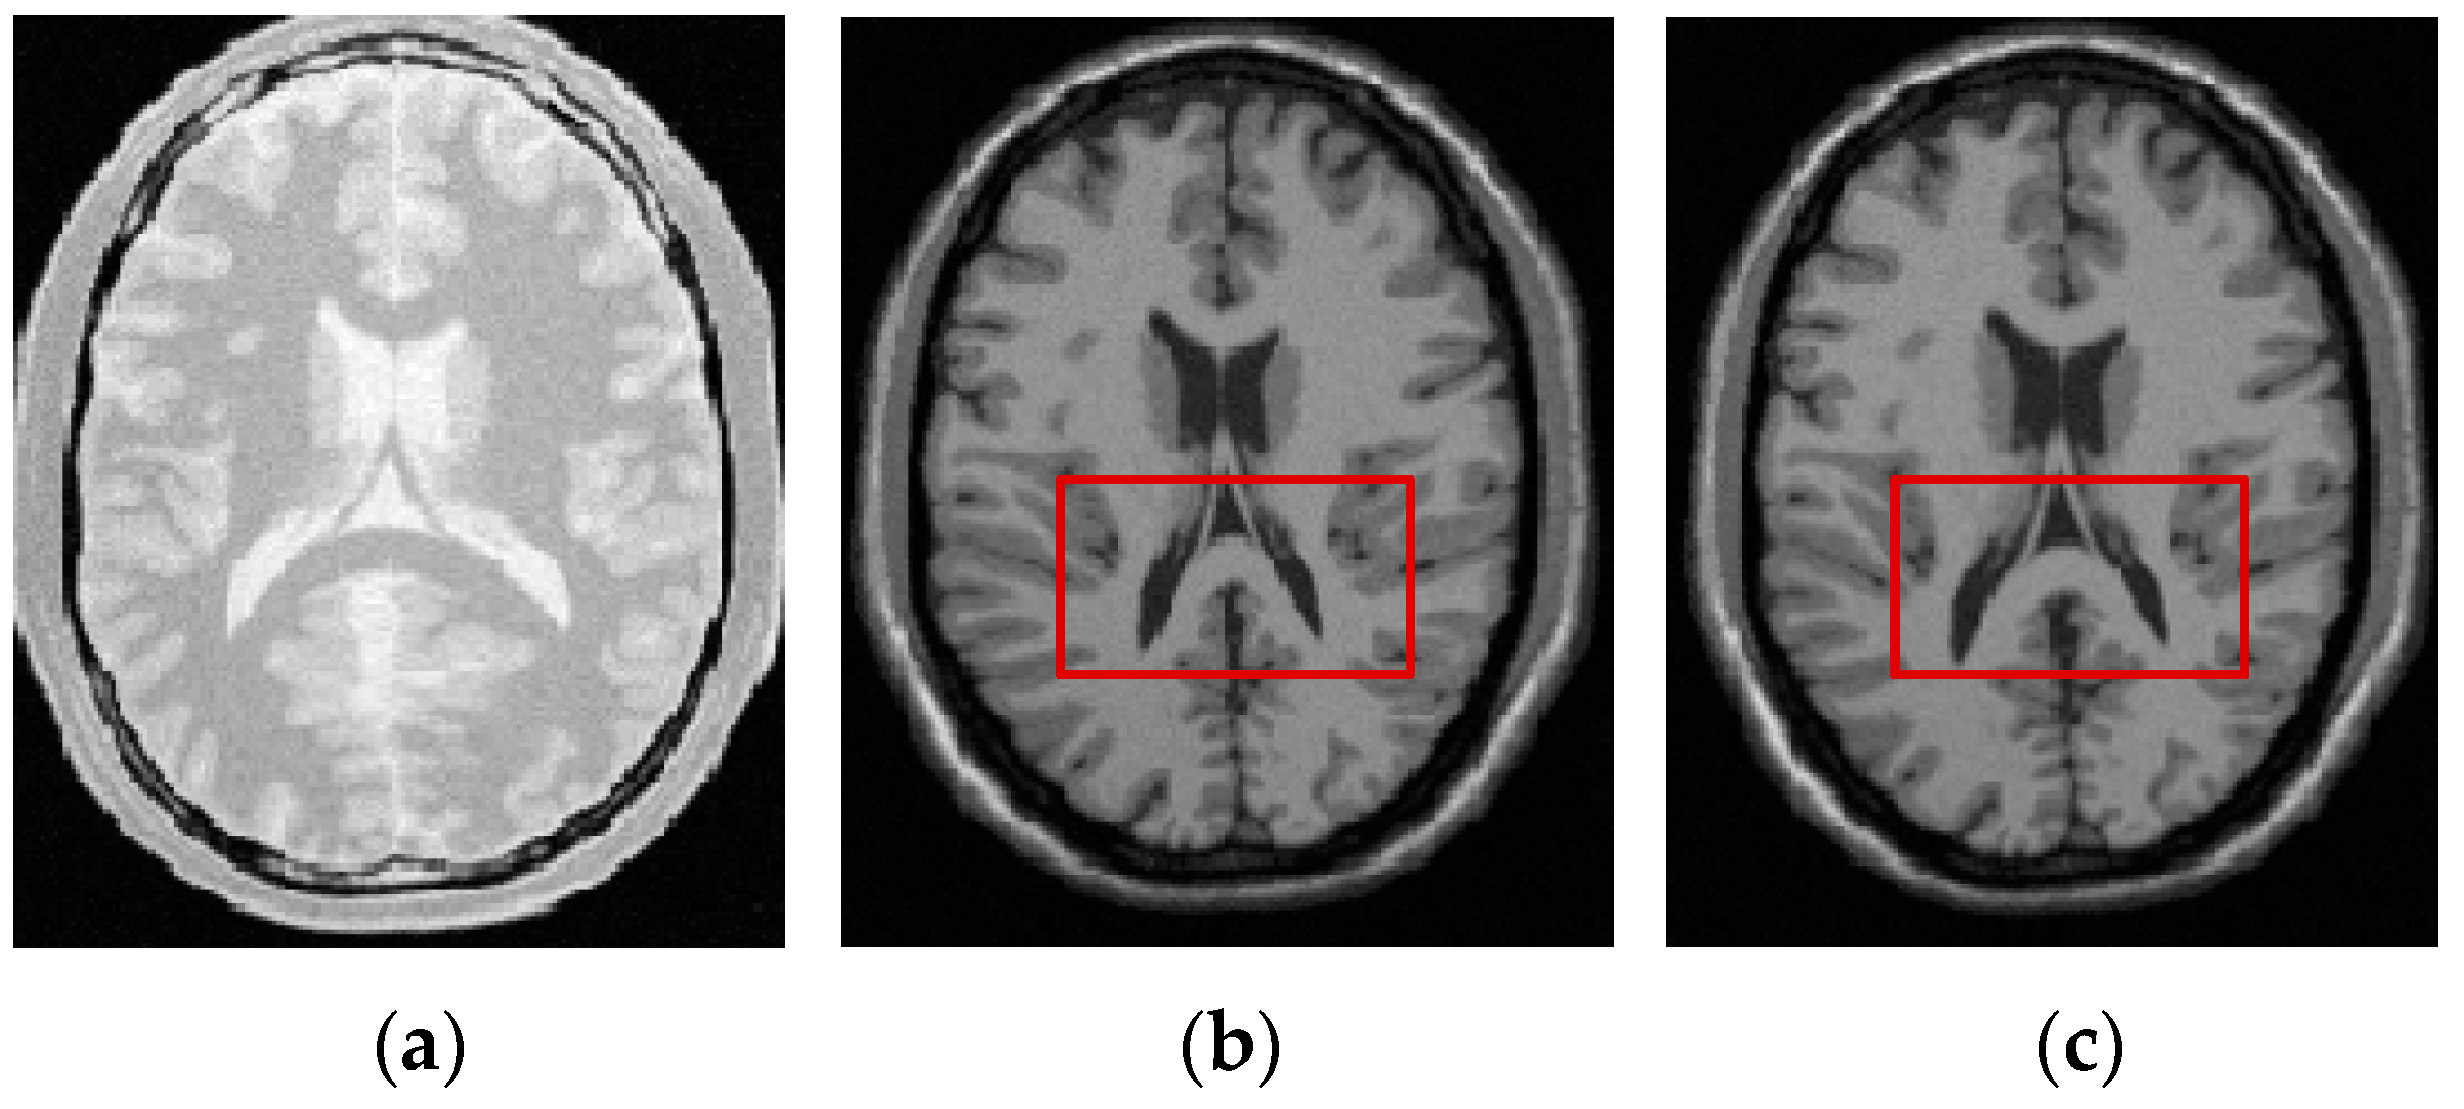

where is the synthetic deformation (i.e., the ground truth generated by using a linear combination of radial basis functions), is the deformation that is estimated by the registration methods, and N denotes the number of landmarks selected manually based on doctors’ advice from the reference images. For each pair of reference and float images, different synthetic deformations will be applied to the float image for 25 times and we will manually select 90 (N = 90) landmarks from each 3D reference image to compute the TRE. The mean of TREs values for registering 25 deformed images will be used to appreciate the registration accuracy. Figure 4 gives an example of chosen landmarks in one slice of simulated 3D PD weighted image and real 3D T1 weighted image for MR image registration, 3D CT image for CT-MR image registration and 3D CT image for CT-PET image registration.

Figure 4.

Landmarks in one slice of three-dimensional (3D) medical images. (a) simulated proton density (PD) weighted image; (b) real T1 weighted image; (c) abdomen computed tomography (CT) image; and, (d) whole-body CT image.